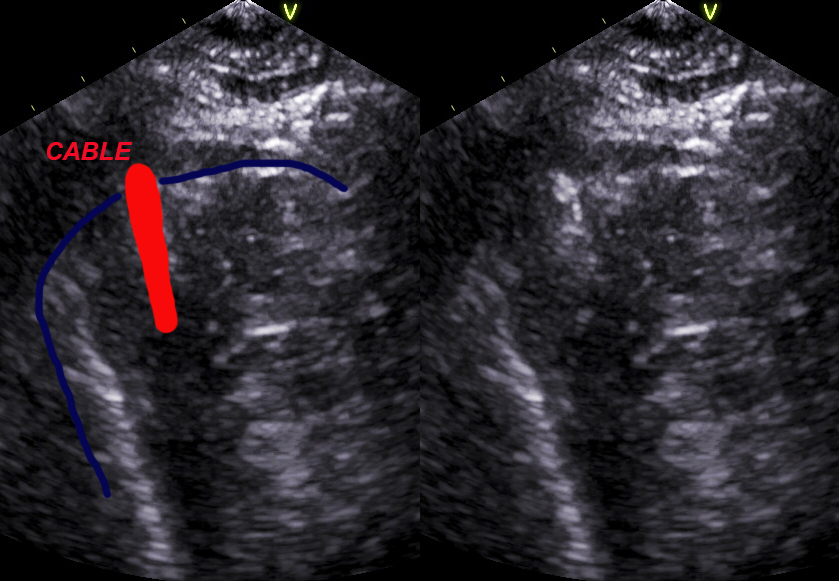

look the position of the cable, apical modified for rv view